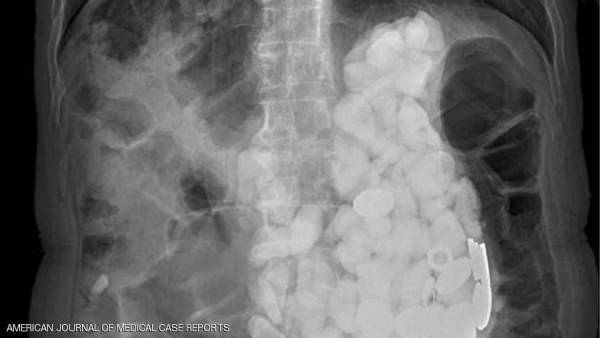

تفاجئ أطباء بعدما عثروا على مجموعة من الحجارة وأغطية زجاجات ونقود معدنية في معدة مريض، أجروا له عملية جراحية لإخراجها بعد أن تناولها أثناء تعرضه لنوبات قلق.

وأجرى أطباء بمستشفى Ilsan Paik بجامعة إنجي الكورية الجنوبية، مجموعة من الفحوصات لمعرفة السبب الكامن وراء هذه الأعراض، حيث شعروا بشيء يشبه الحجارة عند لمس بطنه، واكتشفوا تراكم أجسام في المعدة كلها يصل وزنها إلى كيلوغرامين.

ولم تفلح محاولات الأطباء في إخراج الأجسام من معدة الرجل الذي ولد بإعاقة ذهنية، باستخدام طريقة المنظار نظرا لكثرتها،مما دفعهم للحل الجراحي.